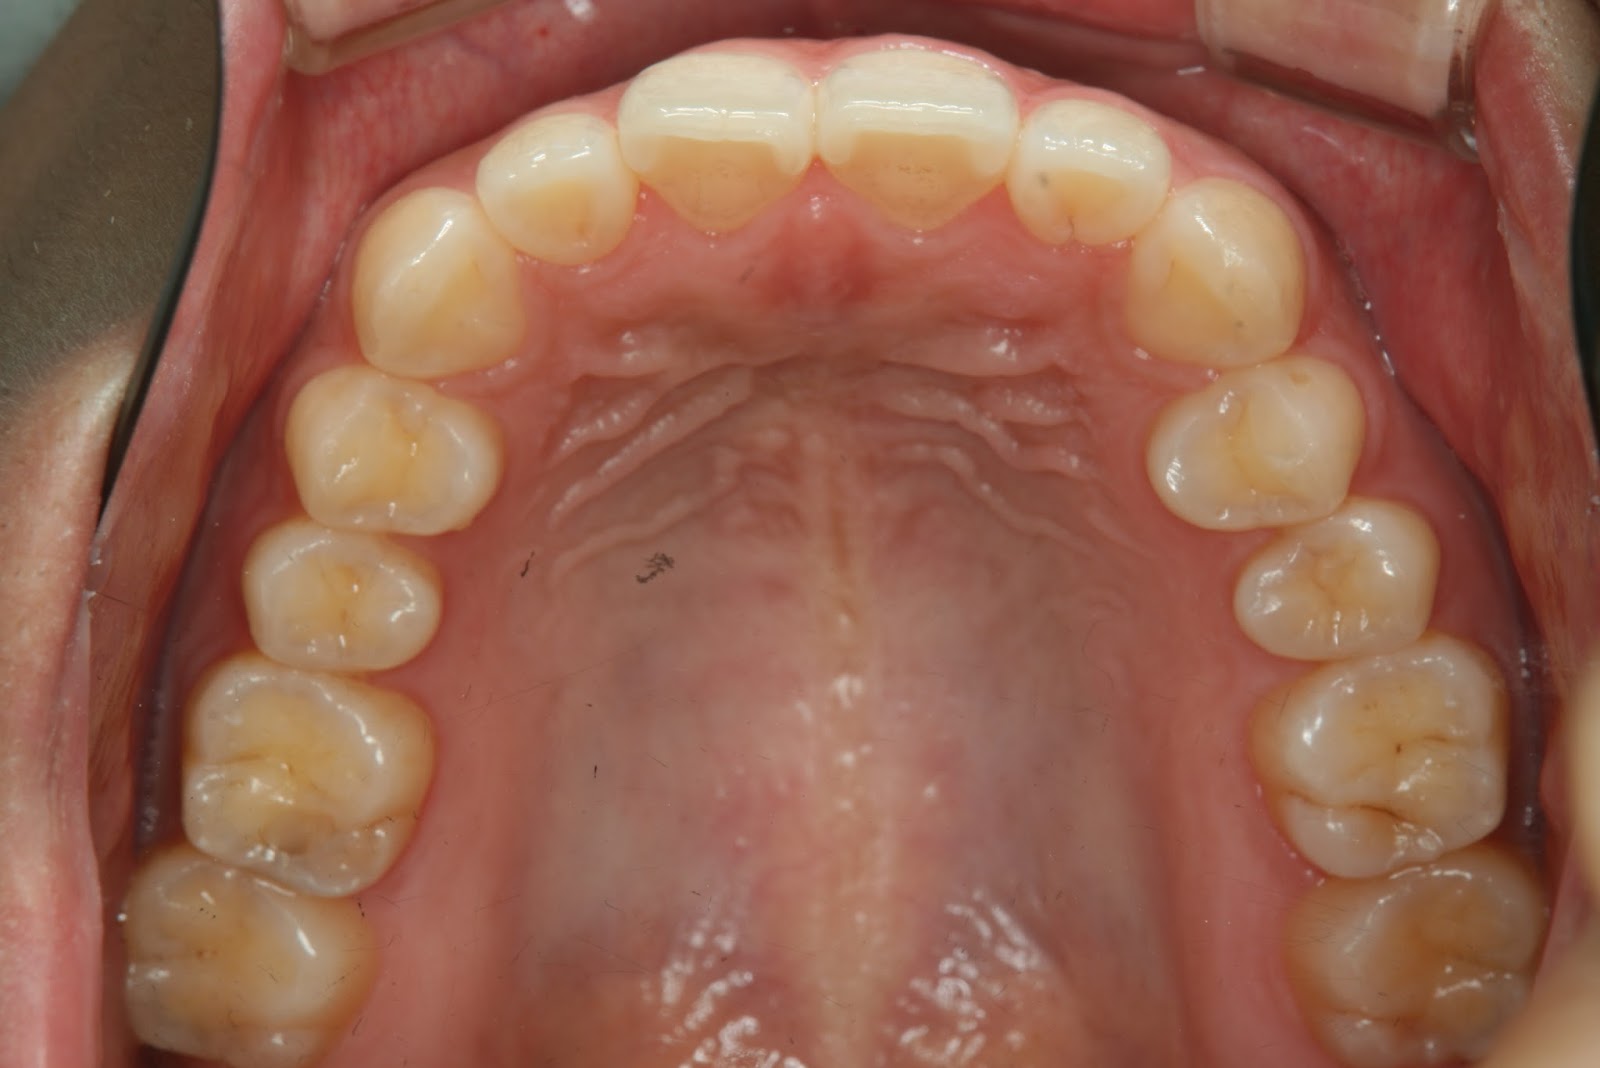

ちょっとグロテスクに感じる方もいるかもしれませんが、私はこんな光景を毎日眺めながら仕事をしています。

ある人が、要らないと思い、手術をして切り取ってしまったそうです。

そうしたらどうでしょう? 食べた物が気管に入りやすくなり、むせるようになってしまったそうです。

何のためにあるのか分からない組織ですが、誤嚥を防ぐという大切な役割りがあったのです。